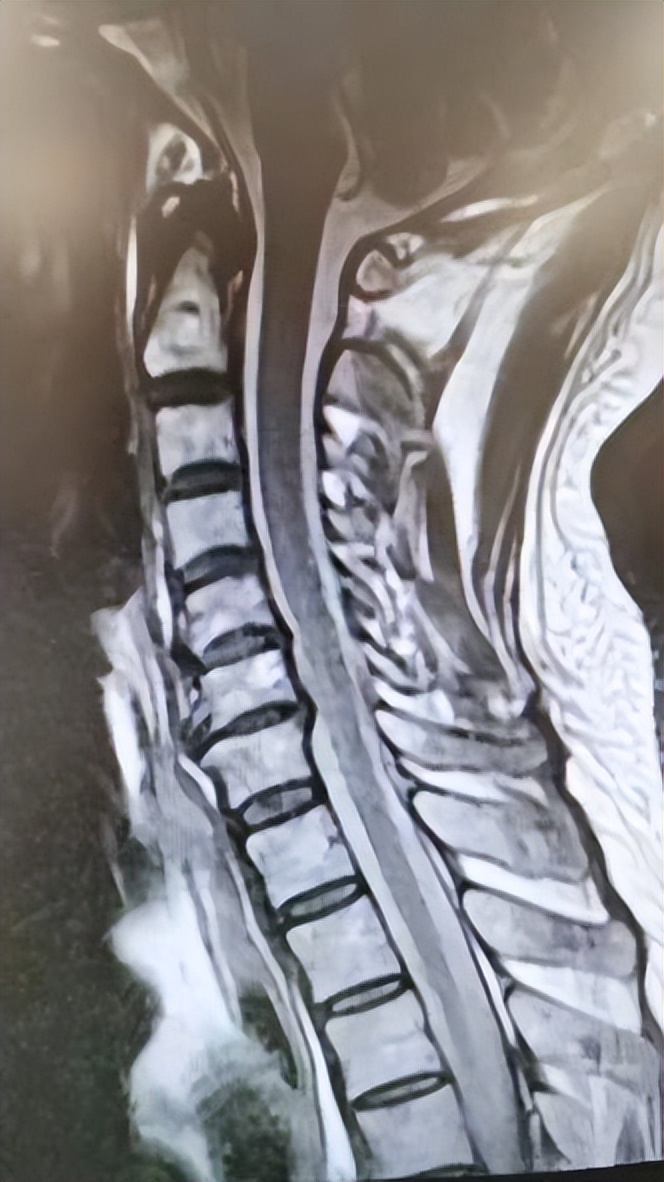

55岁的患者李先生,于4年前无明显诱因间断性出现颈部不适,左上肢疼痛麻木伴头晕、心慌、胸闷,在当地医院诊断为颈椎病后,患者采用保守治疗后症状持续存在,为进一步治疗来西安市红会医院就诊。门诊行MRI检查后提示:颈椎生理曲度变直、骨质增生,颈5-6、颈6-7椎间盘突出、变性。

MRI:颈5-6、颈6-7椎间盘突出、变性